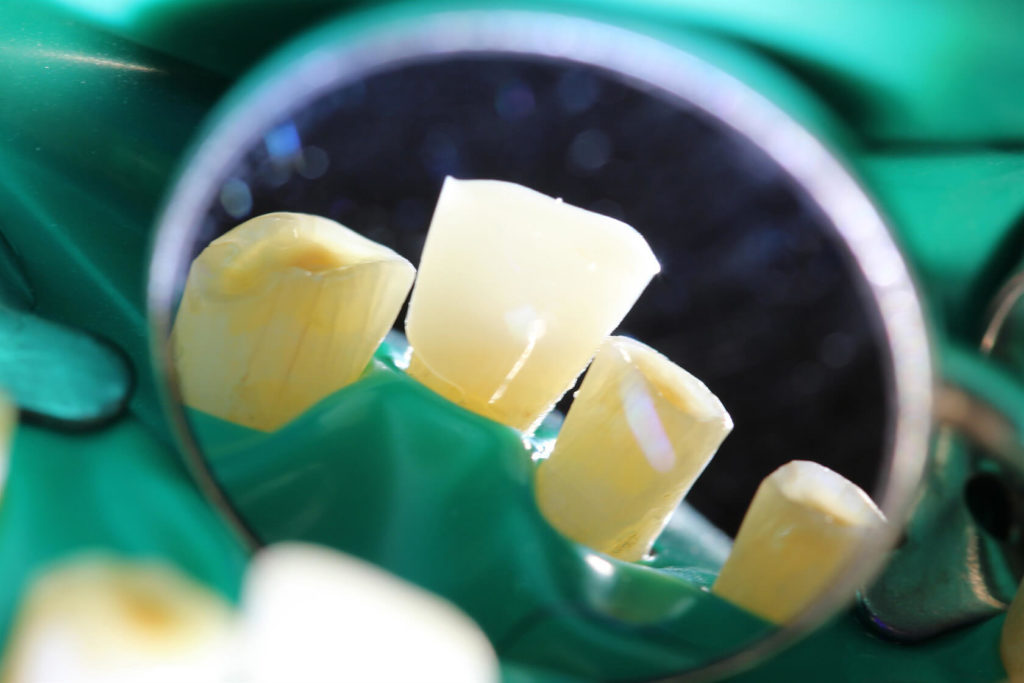

This 50 year old patient was in today for a check-up on his teeth. I had not seen him for 20 months since we restored his lower teeth. We had restored his upper teeth 2 months previous to doing his lower teeth. He came from another neighboring dental office where they don’t do composite rehabs. He has been into this other office for several cleanings since we did his rehab but he smokes, loves his coffee and has lots of stain. Anyway I was wondering how he was making out with his new teeth and he was very satisfied. In his words “no pain or sensitivity or problems”. So I was quite happy with his rehab. His wife came as well and we knew each other from 30 years ago when my daughters and I were riding horses in the same horse club. There were a few air bubbles that I didn’t like and a small open margin that I repaired and that was all he needed to spiffy him up.